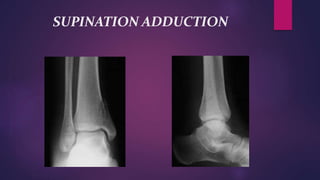

 SUPINATION ADDUCTION INJURY

* Talus is forcibly adducted in the mortise

* Compressive force- medial ankle structures

* Traction force- lateral ankle structures

* Partial or complete disruption of the

components of lateral ligaments of the ankle

SUPINATION ADDUCTION

INJURY

 SPRAINED ANKLE

*Partial lateral ligament injury with a

tear of the Anterior Talofibular fasciculus only.

*forcible inversion of the plantar

flexed foot

* if the adduction force then stops, this

will be the only injury i.e. an isolated injury of

the Anterior Talofibular ligament.